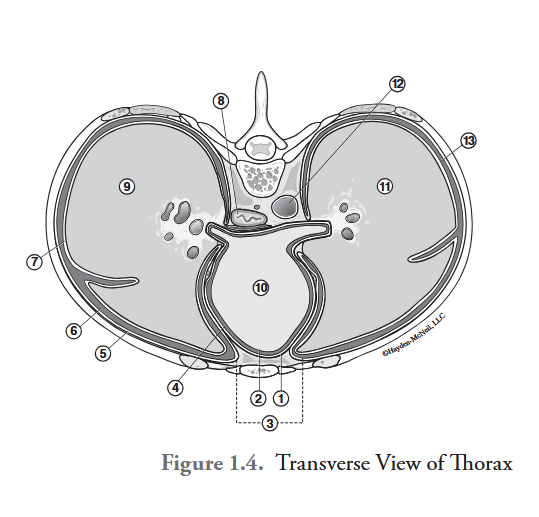

What is labeled #1?

parietal pericardium

What is labeled #2?

visceral pericardium (epicardium)

What is labeled #3?

mediastinum

What is labeled #4?

pericardial cavity

What is labeled #5?

parietal pleura

What is labeled #6?

right pleural cavity

What is labeled #7?

visceral pleura

What is labeled #8?

esophagus

What is labeled #9?

right lung

What is labeled #10?

heart

What is labeled #11?

left lung

What is labeled #12?

descending aorta

What is labeled #13?

left pleural cavity